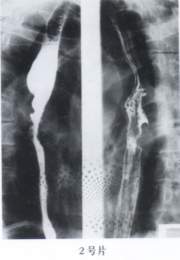

先天性食管狹窄病例例2 女,6個月。因3個月來嗆咳

嘔吐就診。患兒消瘦,雙肺聞及痰鳴音,余無陽性體徵。食管碘油造影顯示食管中段有2.5cm狹窄段,其上方食管輕度擴張。經食管擴張治療治癒。

討論:先天性食管狹窄臨床罕見。可有三種類型:(1)食管蹼性狹窄;(2)食管肌肥厚;(3)食管壁內異位支氣管組織。本2例均經食管碘油造影證實為肌肥厚性狹窄,並經食管擴張術治療好轉或治癒。

本病特點是,生後多無症狀,直至添加半流或固體食物時即發生嚴重嗆咳及嘔吐,常引起吸入性肺炎及營養不良。食管造影顯示食管有數厘米狹窄段,多位於食管中段或中下段,狹窄上方食管輕度擴張。食管造影宜採用胃管插入食管後,在X線下緩慢注入碘油為佳,一旦發現碘油較快返流時,立即將其回吸,可防止或減少氣管吸入。比套用鋇劑造影安全。